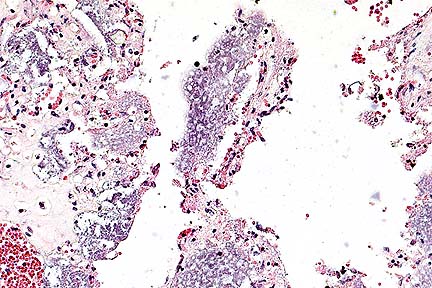

Alveolar macrophages containing numerous gram-negative bacilli and abundant intra-alveolar hemorrhage in a dog with E. coli pneumonia. (Brown-Hopps, 400X, 37K)

Contributor's Diagnosis and Comments: Severe hemorrhagic pneumonia. Cause: Escherichia coli.

There are diffuse hemorrhages within the alveoli. Large numbers of small gram-negative rods are present free in the alveolar hemorrhagic fluids and within the cytoplasm of large foamy macrophages. Focal accumulation of these large foamy macrophages and few neutrophils are observed within alveoli. Lesions were not observed in the intestines and lymphoid organs.

AFIP Diagnosis: Lung: Pneumonia, hemorrhagic, acute, diffuse, severe, with numerous intrahistiocytic and extracellular bacilli, Labrador Retriever, canine.